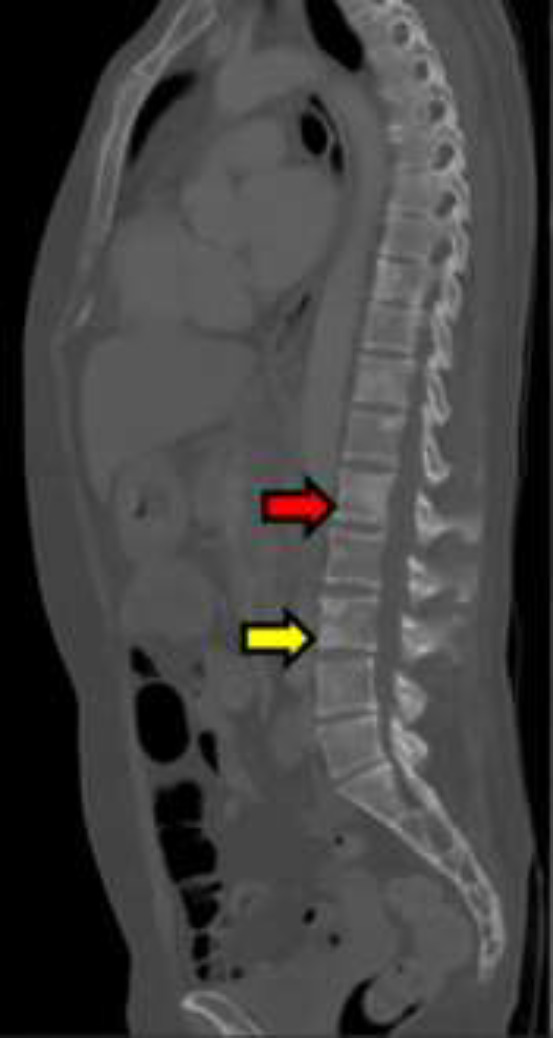

Case presentation: A 51-year-old woman presented with severe headache, vomiting, dizziness, blurred vision, tinnitus, bradyphrenia, reduced verbal fluency, sixth cranial nerve paresis, and non-reactive anisocoric pupils. Pleocytosis was found, with positive cytology for metastatic adenocarcinoma in cerebrospinal fluid, and a solid gastric mass defined as poorly differentiated adenocarcinoma. Due to her condition, the patient did not receive oncological management, evolving unfavorably and passing away twenty days later. Leptomeningeal carcinomatosis should be considered in patients with advanced cancer and meningeal symptoms. It is more predominant in women, with an average age of 53.84 years. Clinical presentation of leptomeningeal carcinomatosis varies, and diagnosis involves neuroimaging and cerebrospinal fluid cytology. Prognosis is unfavorable, often leading to fatality. Treatment protocols lack standardization, and personalized approaches, including targeted and systemic therapies, are explored for improved outcomes. The exceptional aspect of our case lies in the unique diagnosis of an abdominal tumor following the manifestation of neurological symptoms.

Abstract Image